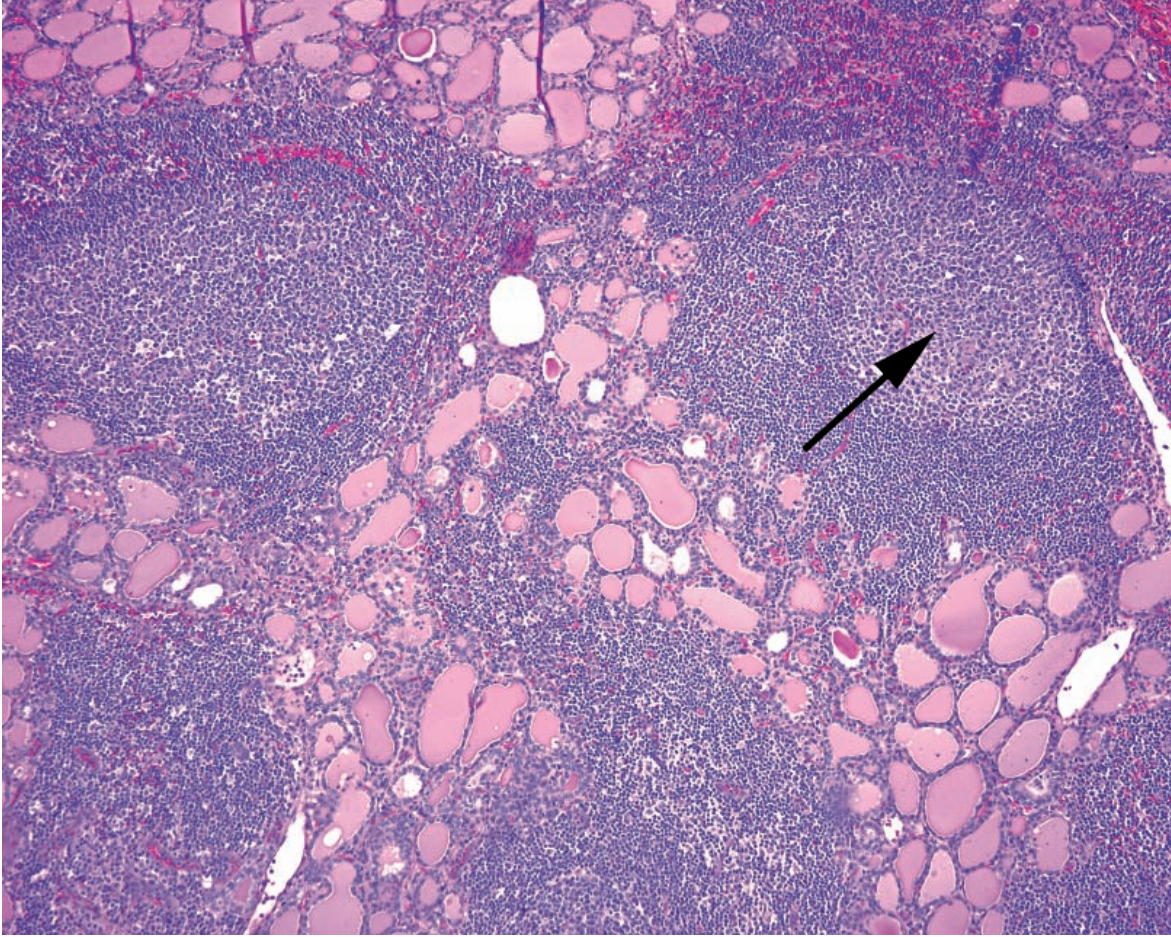

Lymphocytic thyroiditis

Hashimoto’s Thyroiditis

Arrow: Germinal center in lymphoid aggregate